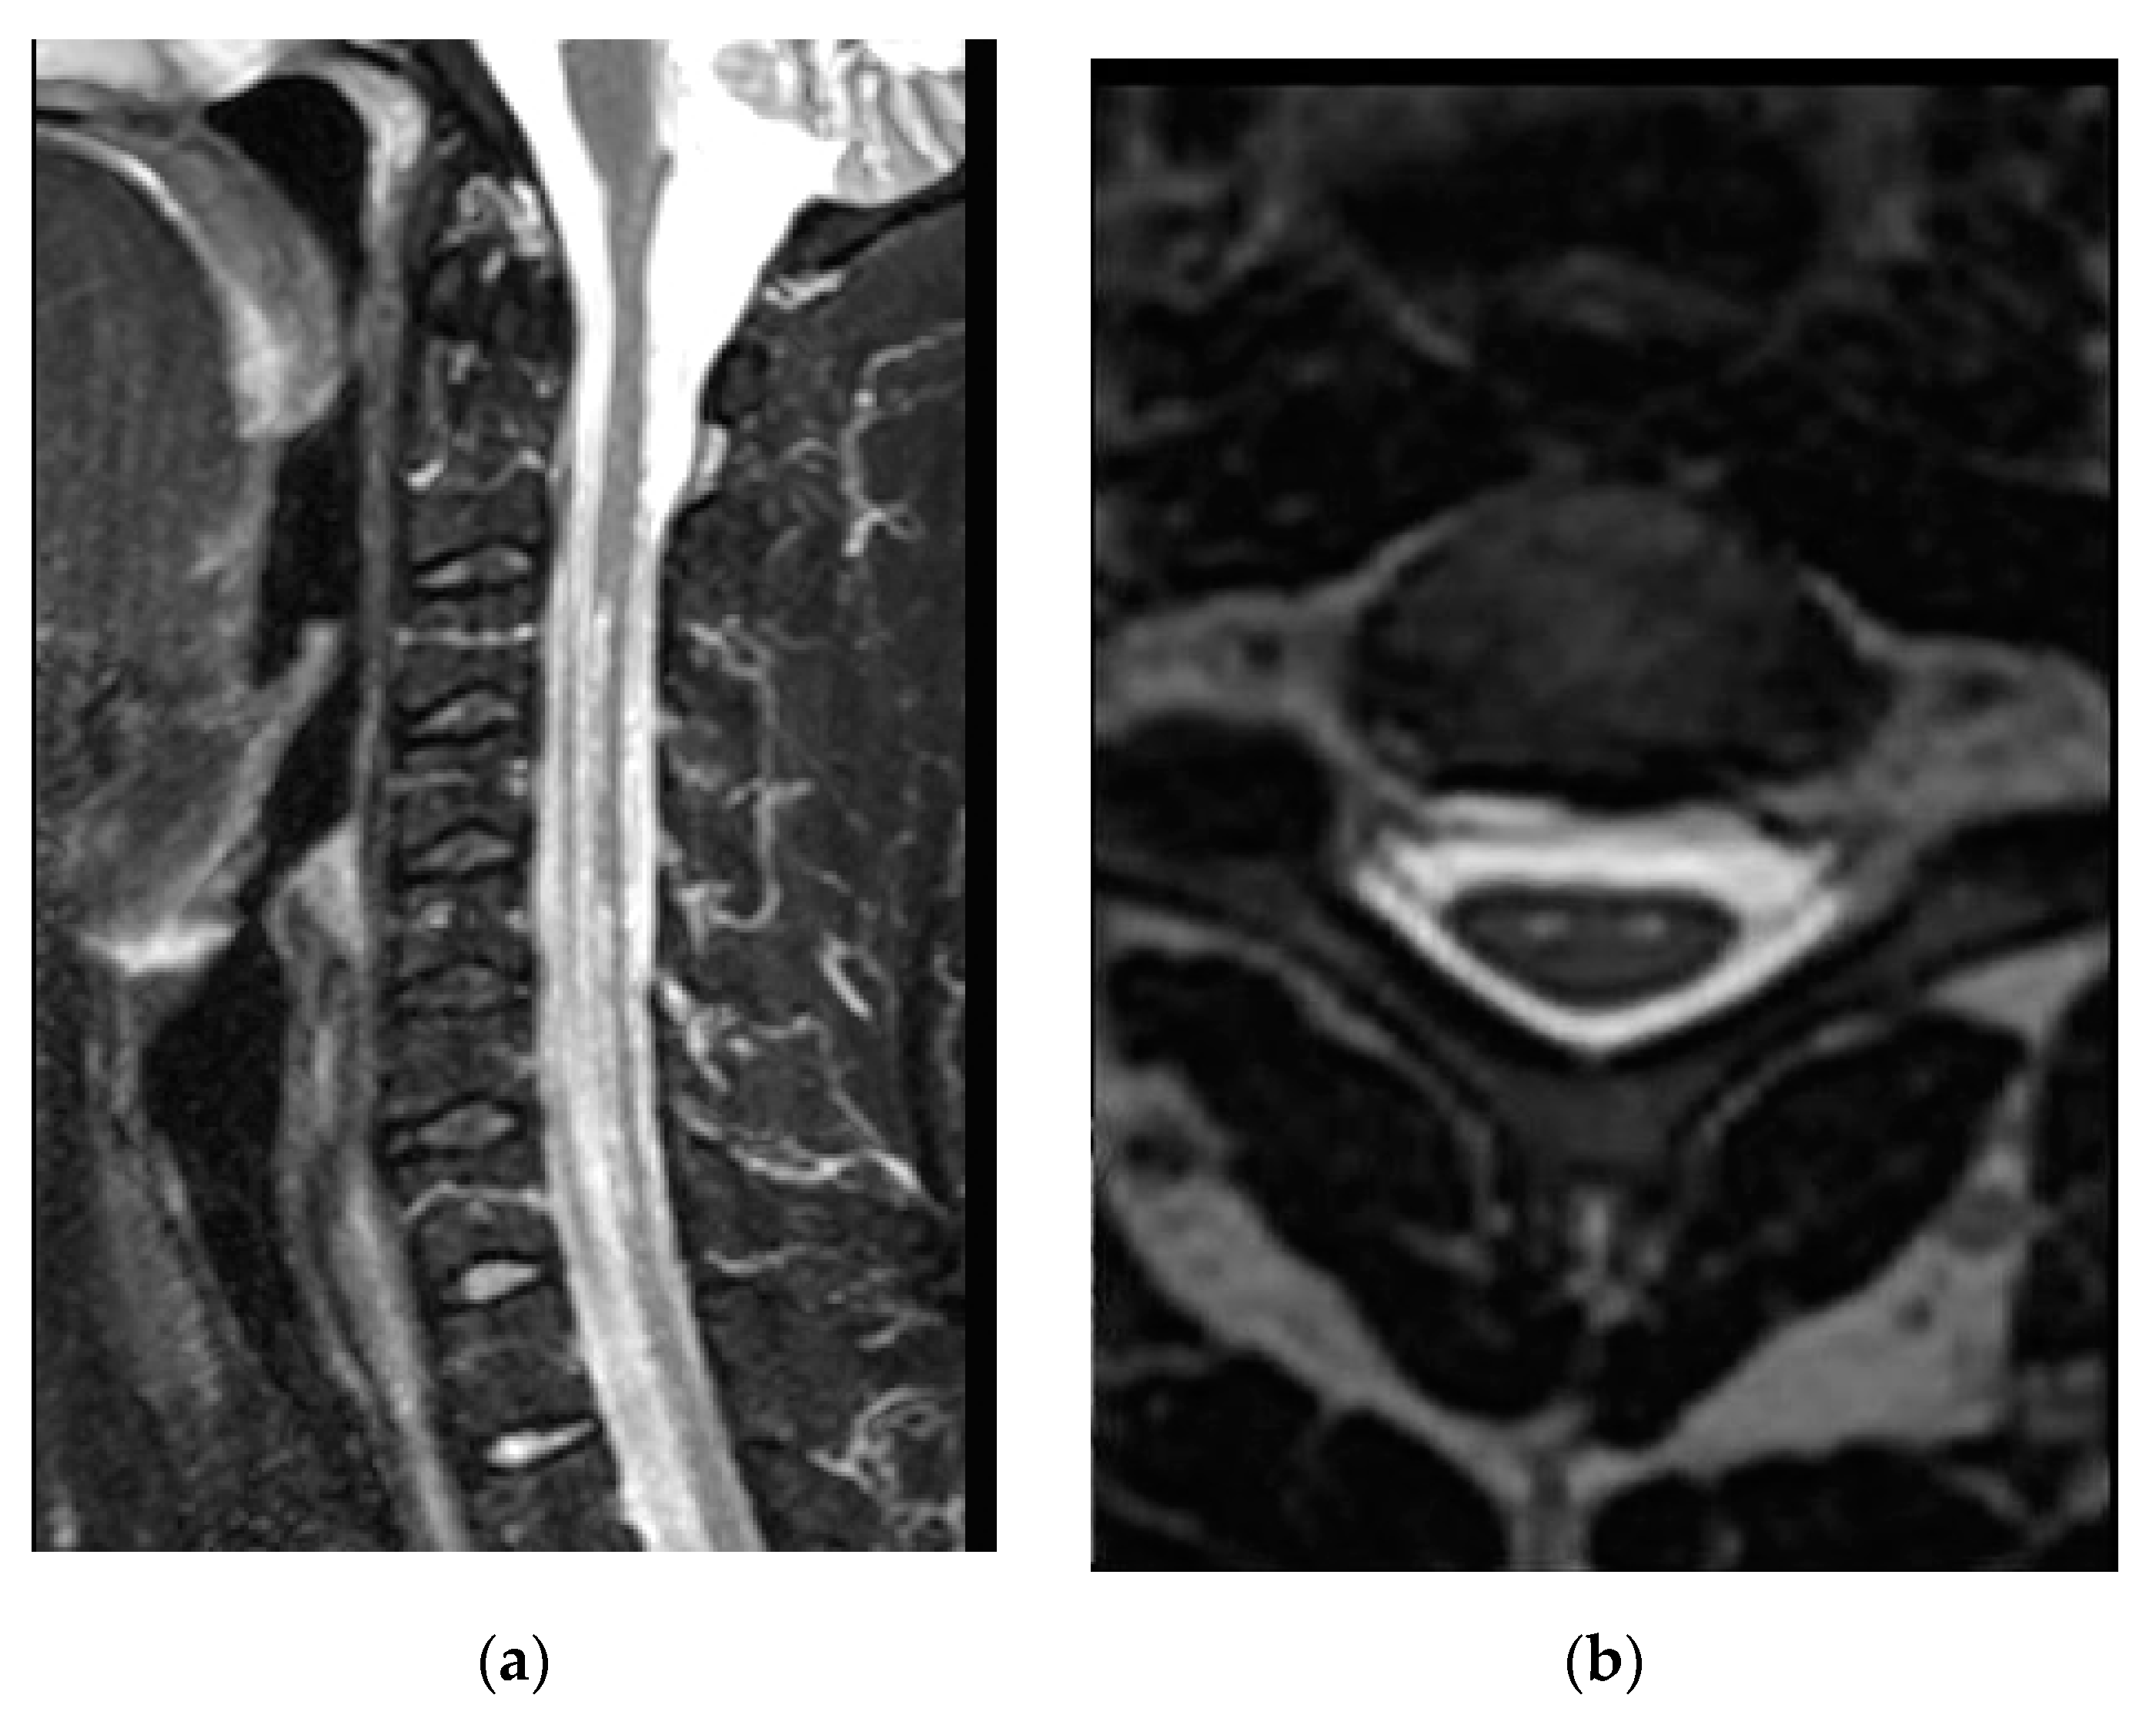

| Reporting results | Regarding DCM, the “snake-eye” appearance was regarded as a negative prognostic factor in 144 cases. In particular, in Mizuno’s study, the improvement ratio determined by JOA score was 32.2% in SEA (mean post-operative mJOA score of 12.9), 47.1% in non snake-eye appearance (NSEA), and 50% (p < 0.01) in control cases in which high signal intensity was absent. |